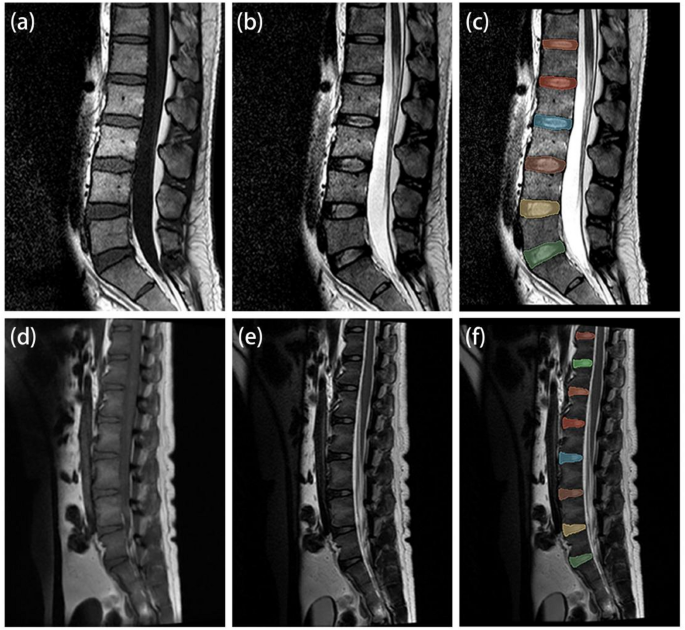

MRI cases of human and experimental monkey. (a–c) Images in a 32-year-old man human. (d–f) Images in a 20-year-old male experimental monkey. (a) and (d) T1-weighted imaging. (b) and (e) T2-weighted imaging. (c) and (f) segmented intervertebral disc regions of interest.

The regions of interest (ROIs) were manually segmented in 3D Slicer software in the median sagittal plane of the target disc and included the entire nucleus pulposus, annulus fibrosus, and endplate (Fig. 2). The ROIs were initially segmented on the T2WI and subsequently replicated on the T1WI by two specialists (Zhiyu Z., J.W.). One of the specialists (Zhiyu Z.) performed 2 analyses, at least 1 week apart; the ROIs outlined the second time were selected for the RF analysis and modeling studies.